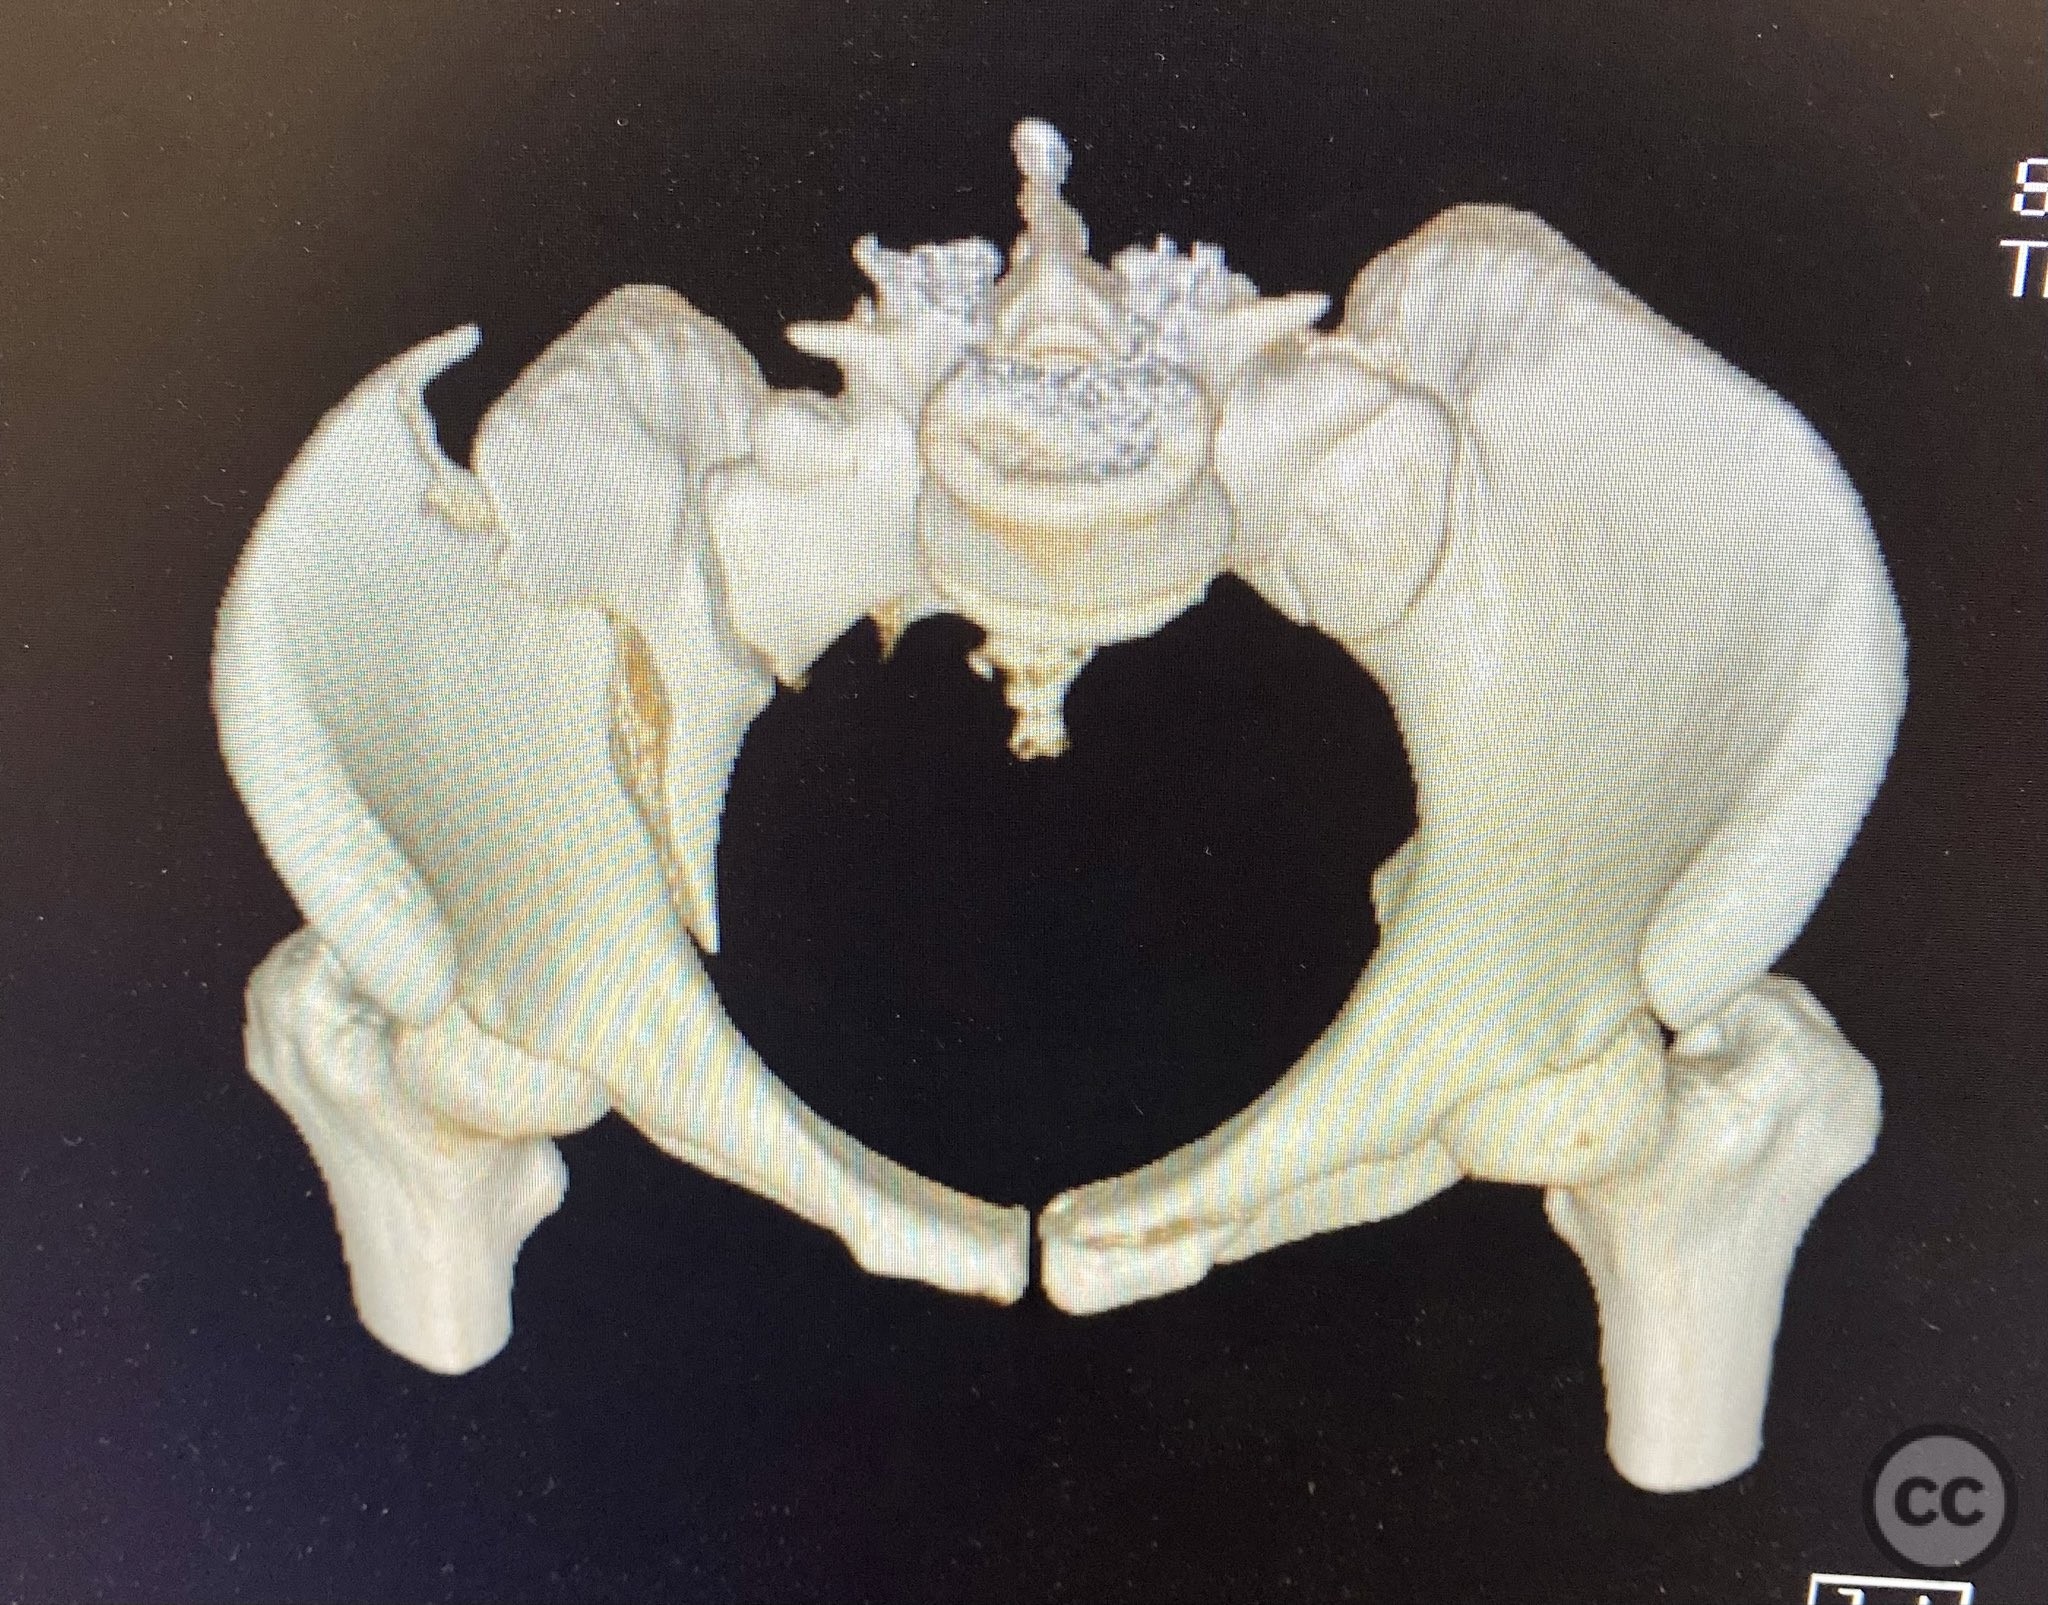

Clinical and radiological findings:  The patient presented following trauma with an unusual, significantly displaced right iliac fracture, accompanied by left-sided sacral and parasymphyseal ramus fractures. Initial AP pelvic radiography demonstrated the complex injury pattern. CT imaging provided detailed characterization of the iliac and sacral fractures, including assessment of displacement, bone quality, soft tissue status, and overall body habitus. No neurovascular compromise was reported. AO/OTA classification: Right iliac fracture 61B2.3 (partial unstable, lateral compression injury), left sacral fracture Denis zone I, left parasymphyseal ramus fracture.

Planning remarks:  The preoperative plan included initial application of bilateral distal femoral traction to achieve provisional reduction, particularly targeting the sacral displacement. Definitive surgical management consisted of percutaneous stabilization of the left sacral fracture and open reduction with internal fixation (ORIF) of the right iliac fracture via an anterior approach, with planned placement of pelvic brim cancellous screws.

Anatomical surgical approach:  A standard anterior ilioinguinal approach was utilized for the right iliac fracture. Dissection proceeded through the skin and subcutis, with identification and protection of the lateral femoral cutaneous nerve. The external oblique aponeurosis was incised, and the iliacus muscle was elevated subperiosteally from the internal iliac fossa to expose the fracture site. Reduction was achieved under direct visualization, followed by internal fixation with a contoured plate and pelvic brim cancellous screws, ensuring all implants were contained within the osseous fixation pathway. The left sacral fracture was stabilized percutaneously under fluoroscopic guidance.

Bilateral distal femoral traction resulted in excellent reduction of the sacral fracture but did not adequately reduce the iliac displacement. Percutaneous fixation of the sacrum was performed first, followed by open reduction of the iliac fracture. Intraoperative imaging confirmed that all implants were fully contained within the available osseous corridors, avoiding extraosseous penetration. The complexity of the iliac fracture required careful anatomical reduction and implant placement along the pelvic brim.

Orthopaedic implants used:   Pelvic brim contoured plate, cancellous screws, percutaneous sacral screw(s)